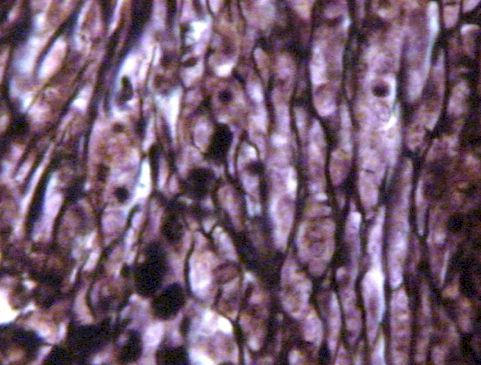

Soft Organ Reticular Tissue

The black reticular fibers (collagen) in the adjacent photo are specially stained to show up. The other lymphatic photos of the node, spleen and thymus are stained to show the numerous cells.

The reticular fibers are very important to give support to the soft organ and to slow the transport of lymphatic cells through the organ so they have time to develop for specifie immunity.